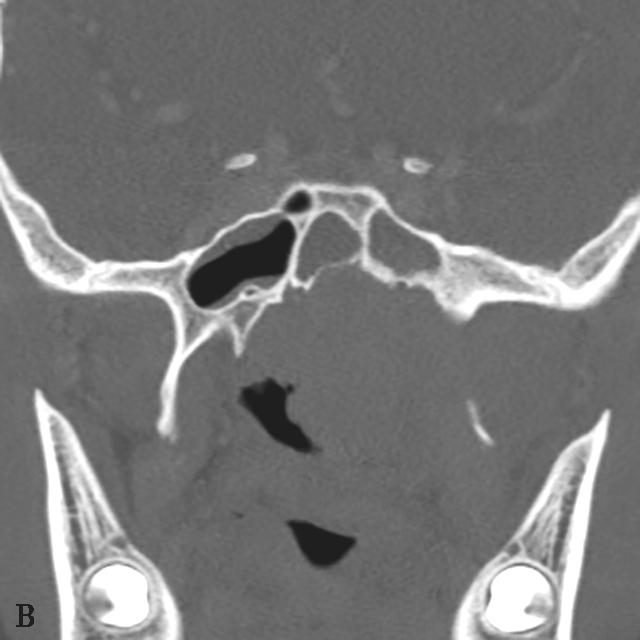

图1-2-5 青少年非角化型鼻咽癌

患者男,14岁,反复间断鼻出血、头晕头痛20余天。A.鼻窦CT横断面骨窗,示鼻咽顶后壁左侧软组织肿块,累及后鼻孔区,邻近左侧岩尖、蝶骨翼突骨质破坏、不完整,边缘毛糙;B.鼻窦CT冠状面重组骨窗,示左侧鼻咽顶后壁软组织肿块,邻近蝶骨翼突溶骨性骨质破坏,累及蝶骨体,边缘毛糙不整;C.鼻咽部MR T 2 WI横断面,示鼻咽左侧壁软组织肿块呈不均匀稍高信号,其间可见条状高信号,未见血管流空影;病变累及左侧翼内肌、窦后脂肪间隙;左侧上颌窦内可见积液呈明显高信号;D.鼻咽部MR T 1 WI横断面,示鼻咽部软组织肿块呈等信号,左侧上颌窦内积液呈低信号;E.鼻咽部MR T 1 WI横断面增强脂肪抑制序列,示鼻咽部病变呈明显强化,累及鼻咽左侧壁、顶后壁并跨越中线累及右侧咽隐窝,右侧咽后间隙淋巴结可见,与软组织肿块同步强化;F.鼻咽部MR T 1 WI冠状面增强脂肪抑制序列,示病变累及左侧咽旁间隙,左侧上颌神经明显增粗强化,并经上颌神经累及左侧海绵窦致其增厚、强化。活检病理符合鼻咽癌(非角化型)